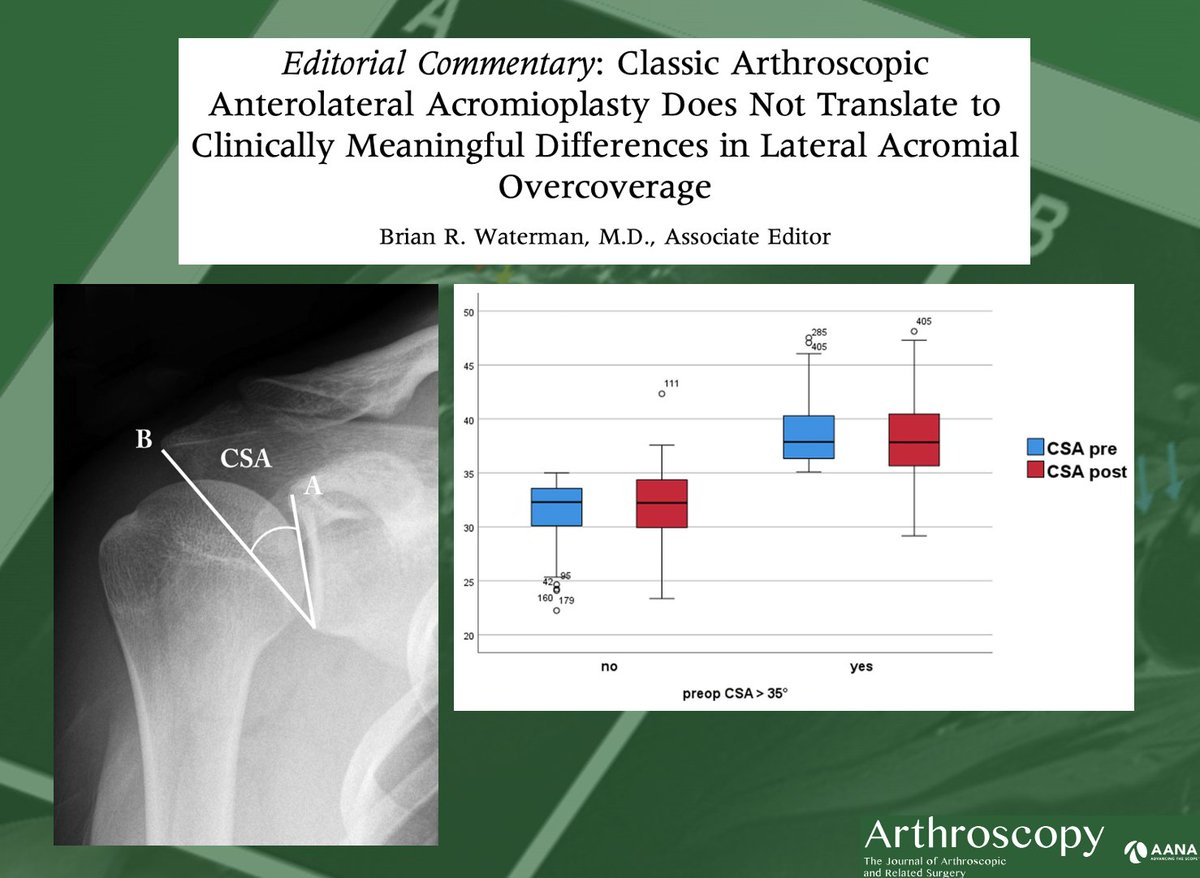

Brian Waterman, MD with his commentary on the clinical usefulness of classic anterolateral acromioplasty vs. lateral acromioplasty in cases of RTC tears with an increased critical shoulder angle. ow.ly/MS6550LGcgt